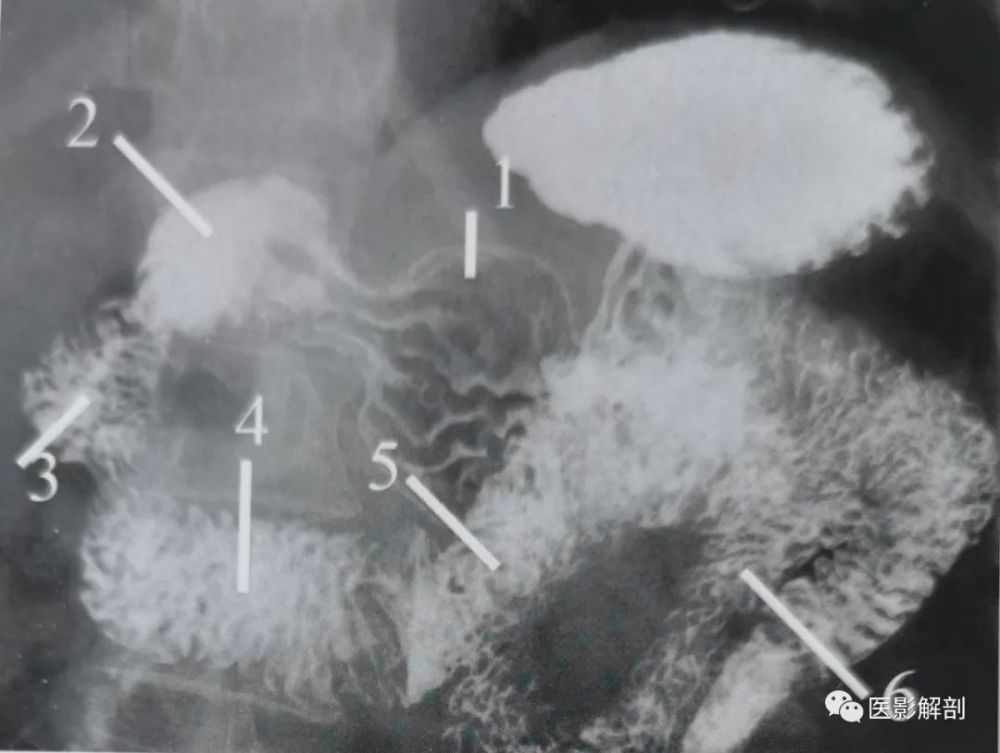

(图) 瀑布型胃(x线钡餐造影)

a:鱼钩型胃 b:牛角型胃 c:瀑布型胃

瀑布型胃:;c. 牛角型胃;d. 无力型胃.胃的分型a.